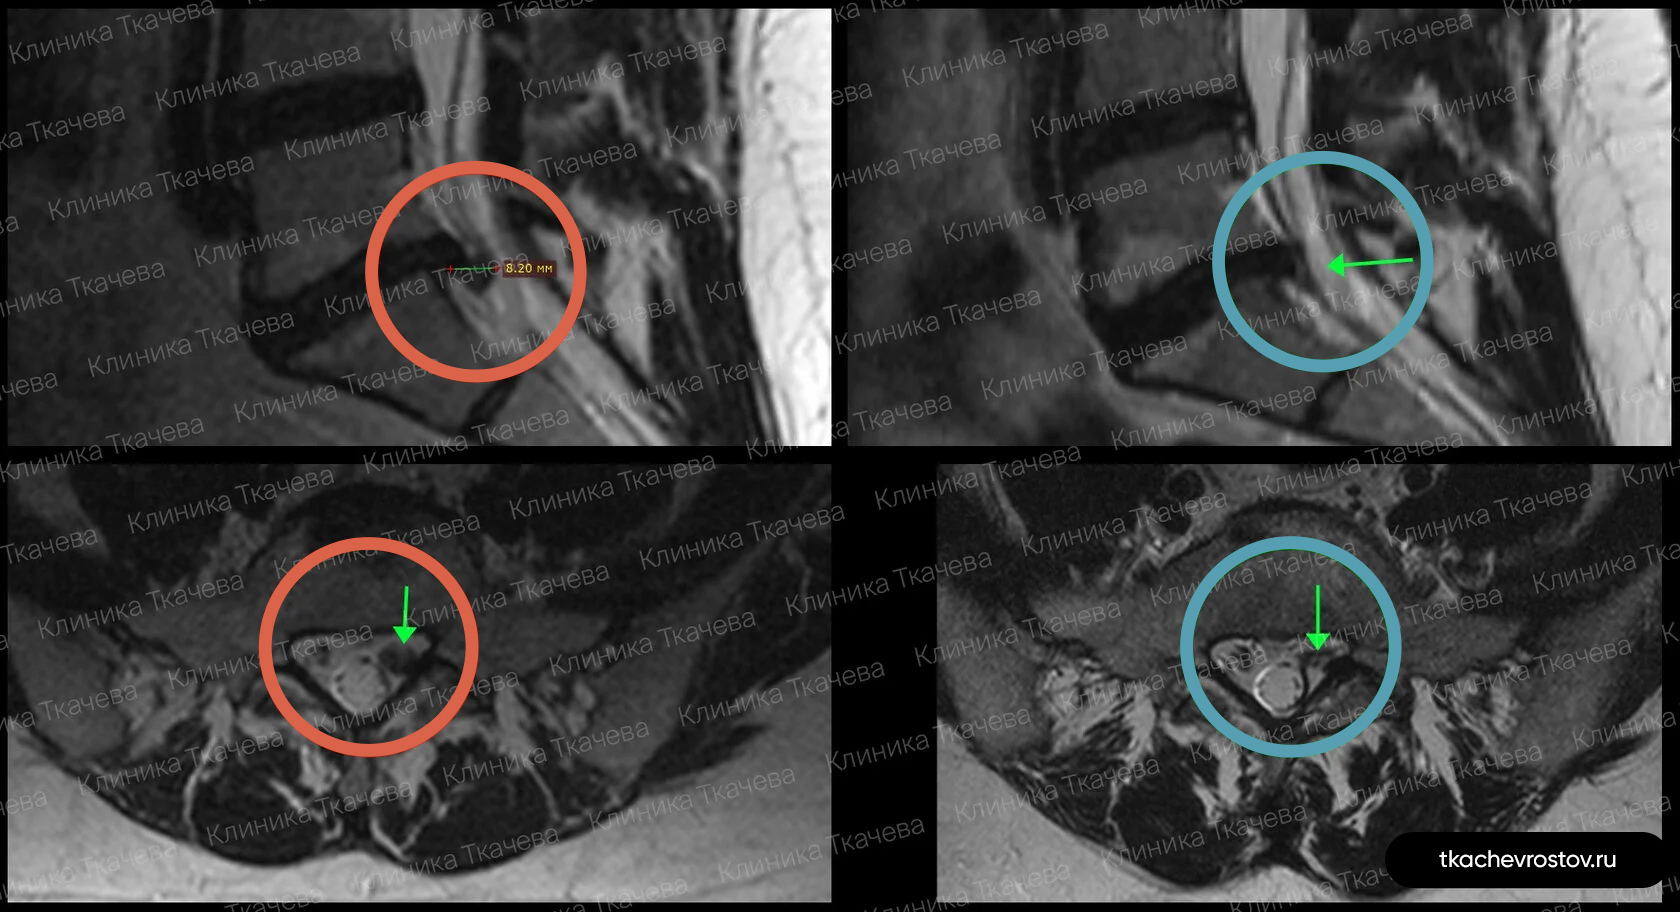

Грыжа в шейном отделе С5-С6

Женщина, работает в медицинской сфере. Полгода лечилась до нас консервативно, 3 нейрохирурга отправили на операцию.

ДО:

- Длительная отрицательная динамика

- Тянущие и простреливающие боли в шее

- Боль, онемение и прострелы в левой руке

- Онемение 4 и 5 пальцев руки

- Усиление боли при смене положения или при длительном сидении

ПОСЛЕ 1 курса:

✓ Наступила резорбция грыжи на 40%

✓ ушли стреляющие боли в шее и руке

✓ Онемение осталось только на подушечках пальцев

ПОСЛЕ 2 курса:

✓ Уменьшение грыжи более чем на 80%

✓ Все болезненные симптомы ушли

Пациентка прошла 2 курса лечения (по 12 дней).